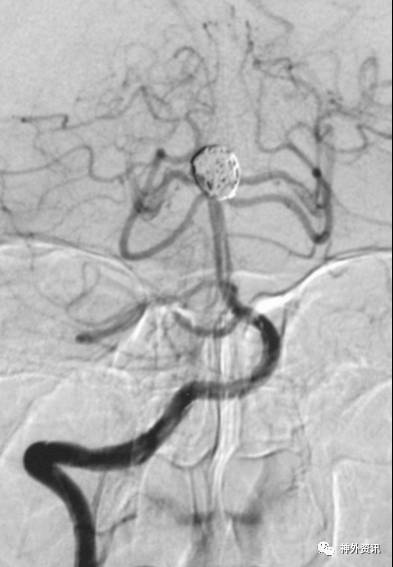

病例一